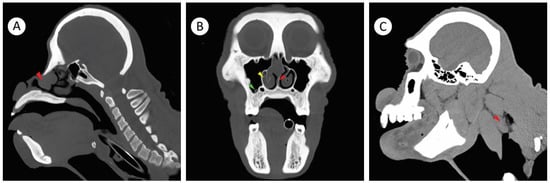

2.3. Computerized Tomography Imaging